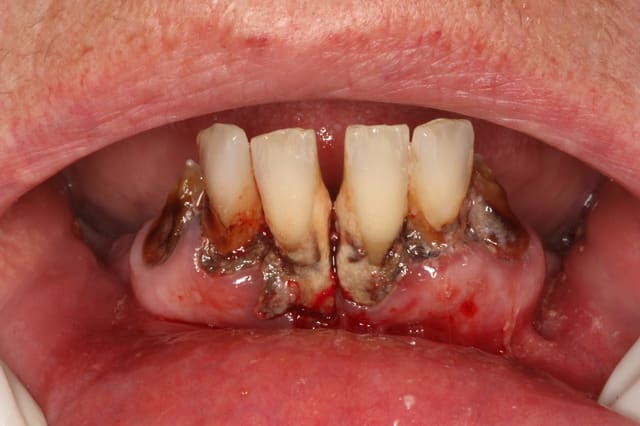

H47 ans avec un brossage annuel et une visite chez le dentiste par décennie.